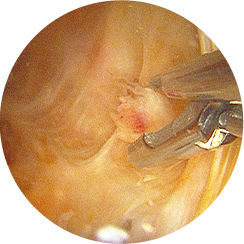

무릎 관절내시경 수술은 1cm 미만의 작은 수술 부위에 내시경과 수술기구를 삽입하여

손상된 연골이나 인대, 이물질 등을 직접 확인하고 정밀하게 치료하는 수술입니다.

관절내시경을 삽입해 내부를 실시간으로 보면서

손상된 부위를 정밀하게 제거하거나 봉합하기 때문에,

CT나 MRI로도 정확히 파악하기 어려운 미세한 연골 손상이나

관절 내부 이상까지 확인하여 보다 정확한 진단과 즉각적인 치료가 가능합니다.

1cm 미만의 절개 부위를 통해

관절내시경을 삽입합니다.

고해상도 영상으로

연골·인대·반월상연골의

손상 부위를 정확히 확인합니다.

특수 미세 기구를 이용해

손상된 부위를 절제하거나,

봉합합니다.